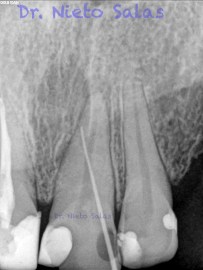

Nos llega a la clínica  este 4.5 con necrosis y periodontitis apical. la instrumentación se realizó con técnica de crown-down con limas K3 (SybronEndo) y la obturación con la técnica de ola continua de Buchanan, el tiempo de trabajo (para mi bastante importante) sobre 70-90 min.

Pero no todo se va a dejar al «poder de la irrigación»,  es muy importante la biomecánica, y la intuición para poder instrumentar esos pequeños conductos laterales que es muchas ocasiones nos dan problemas. Así, pues, os pongo un par de casos que con ayuda de esta «intuición» pudimos hacer un buen tratamiento.

Presentaban un sondaje normal, y sospechamos de que podía tratarse de lesiones por conductos laterales.

Una vez que hemos desbridado biomecánicamente con limas de muy pequeño diámetro, obturamos: